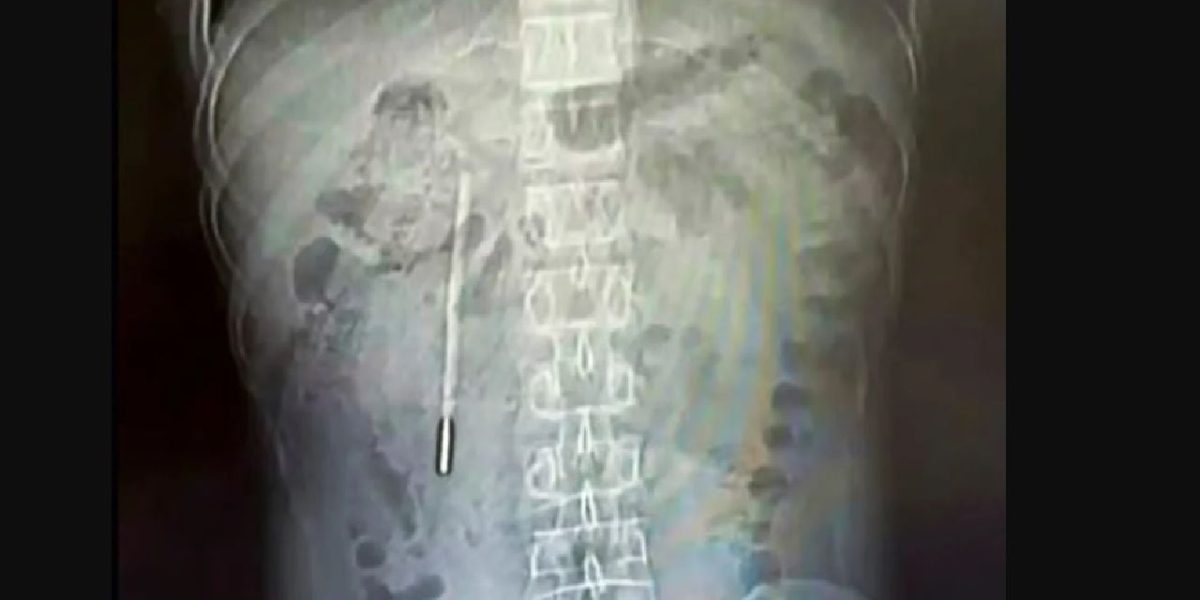

Pacientul, în vârstă de 32 de ani, s-a prezentat la Spitalul Universitar de Medicină Wenzhou din provincia Zhejiang, acuzând dureri abdominale constante. Investigațiile medicale au condus la descoperirea unui corp străin în duoden. Ulterior, o radiografie a confirmat suspiciunile: un termometru cu mercur era poziționat periculos de aproape de peretele intestinal. Această apropiere sugera un risc crescut de perforație și hemoragie internă severă.

Situația s-a agravat, determinându-l pe Wang să caute ajutor medical de urgență. Medicii au decis să intervină chirurgical pentru a îndepărta termometrul. Intervenția a fost un succes, iar termometrul a fost extras intact. Cu toate acestea, marcajele de pe termometru se șterseseră complet, din cauza trecerii timpului.